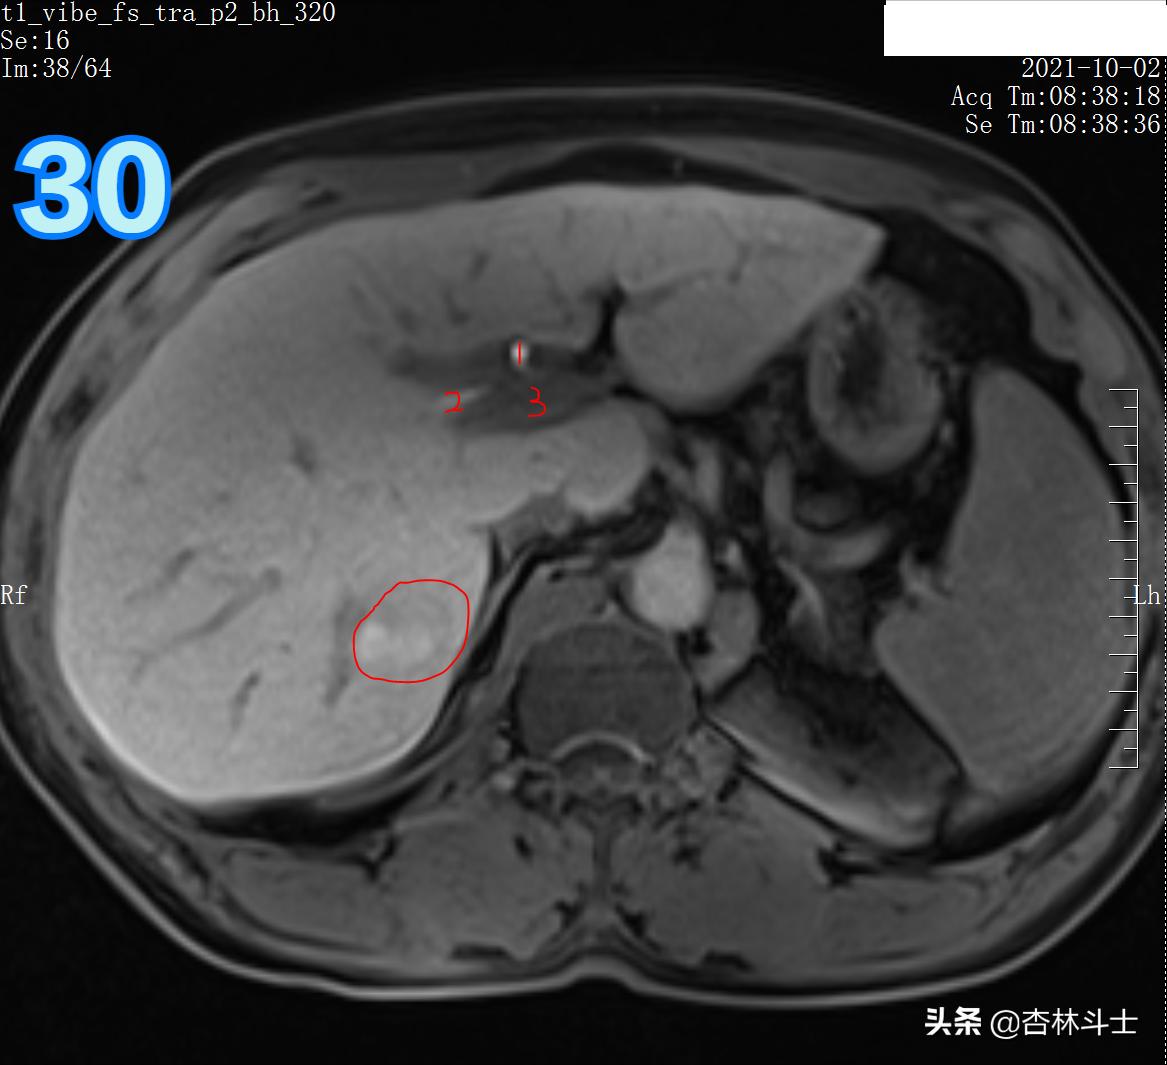

T1压脂肝胆特异期

图30 1、左肝管 2、右肝管 3、门静脉主干

总结:10月份复查,肝右后叶下段新发一个直径约1㎝的结节,T1呈等信号,T2呈稍高信号,弥散加权序列可见弥散明显受限,增强动脉期明显均匀强化,门静脉期出现对比剂廓清,呈略低信号,平衡期信号进一步减低,肝胆特异期未见特异性对比剂摄取呈低信号。增强特征为典型的“快进快出”,影像学上典型的肝细胞癌表现。

结合影像学检查及肝炎病史,两个病灶均考虑肝癌。